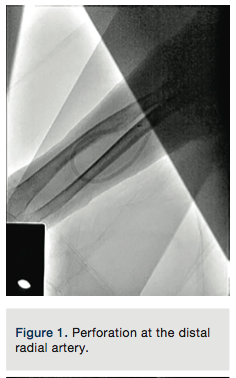

But, more significant is the issue of fully utilizing the information we frequently have in the catheterization suite to potentially prevent some of these complications. When faced with a complication, we frequently fail to notice and utilize some of the details we would normally pay attention to. In this instance, when the operators performed a radial artery angiogram, only the radial and median arteries were visualized (Figures 1 and 4), with no visualization of the ulnar artery. This should have served as a hint that an anatomic variation could exist, and should have led to further delineation of the anatomy, after the lumen was accessed with a guide wire successfully. The other hint that anatomy conducive to severe spasm might exist was the fact the “tortuosity” was deemed severe enough to necessitate using a guide wire to torque the catheter for coronary access. These subtle hints are frequently not attended, and may lead to nerve-wracking complications as in this instance of entrapment. It is evident in the angiogram performed after guide wire removal that this patient did have a “high takeoff” radial artery (Figure 5), known to develop diffuse and severe spasm, creating a perfect environment for entrapment. In the hands of an experienced operator, most of the time severe spasm occurs in the setting of anatomic abnormalities.